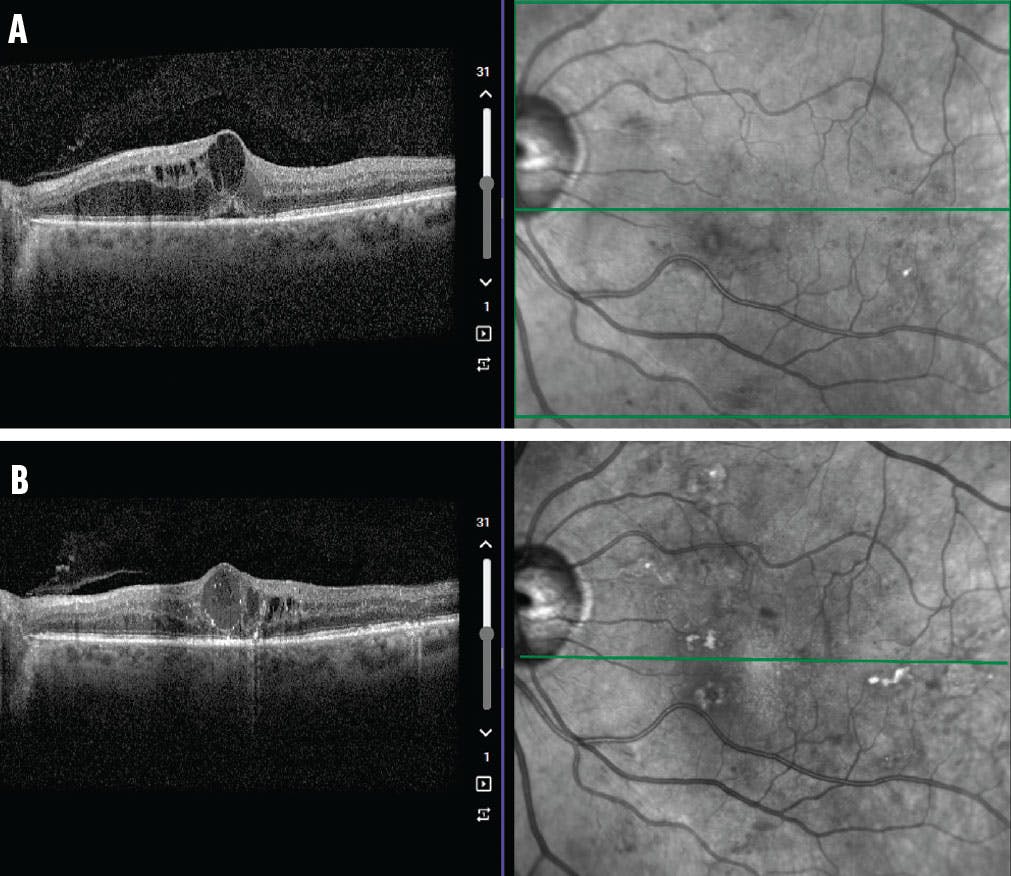

<p>Figure. This patient presented with center-involving DME and a baseline VA of 20/40 (A). Three years later (B), his VA is 20/50 after 11 anti-VEGF injections, eight dexamethasone implants, and focal laser treatment. He continues receiving treatment due to persistent center-involving DME, highlighting the need for more durable treatment options.</p>

Figure. This patient presented with center-involving DME and a baseline VA of 20/40 (A). Three years later (B), his VA is 20/50 after 11 anti-VEGF injections, eight dexamethasone implants, and focal laser treatment. He continues receiving treatment due to persistent center-involving DME, highlighting the need for more durable treatment options.